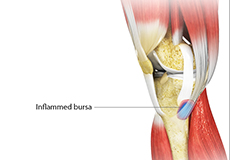

Goosefoot Bursitis of the Knee

A bursa is a small fluid-filled sac found between soft tissues and bones. It lubricates and acts as a cushion, decreasing the friction between bones when they move. Bursitis refers to the inflammation and swelling of the bursa.

Kneecap Bursitis

Bursitis refers to the inflammation and swelling of the bursa. Inflammation of the bursa in front of the kneecap (patella) is known as kneecap bursitis or prepatellar bursitis.

Pes Anserine Bursitis

Bursitis refers to the inflammation and swelling of a bursa. A bursa is a small fluid-filled sac found between soft tissues and bones that lubricates and acts as a cushion to decrease friction between bones when they move.